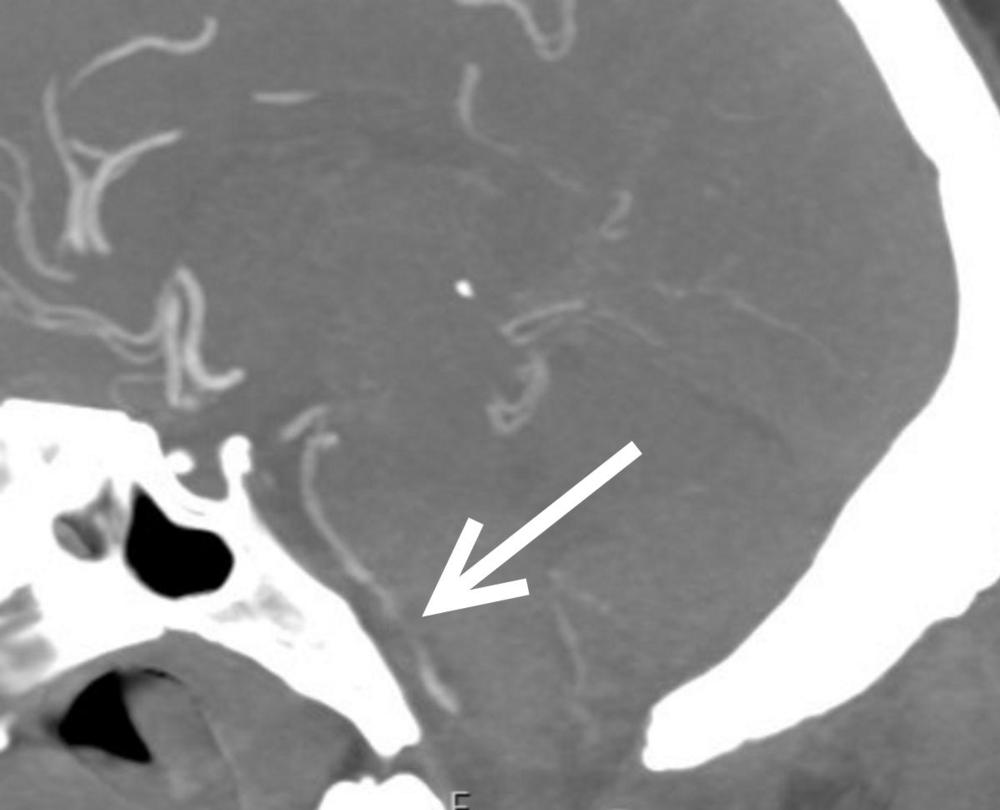

Figure 2. CT of the brain blood vessels of a SARS-CoV-2-positive patient shows a nearly blocked basilar artery (arrow) next to the brain stem. The patient needed an emergency procedure to open the artery.

Figure 3. CT of the brain’s blood vessels shows a nearly blocked artery next to the brain stem. The patient needed an emergency procedure to open the artery.

Figure 4. CT of the brain’s blood vessels shows a nearly blocked artery next to the brain stem (arrow). The patient needed an emergency procedure to open the artery.